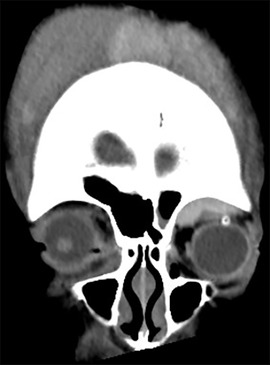

A 16-year-old male patient with Lennox-Gastaut syndrome and developmental disability was admitted to the hospital two weeks after a head injury due to increased swelling and ecchymosis of left eyelid and suspicion of compressive optic neuropathy of the left eye due to massive exophthalmos (Figure 1). A 16-year-old male patient suffering from Lennox-Gastaut syndrome and developmental disability undergoing follow-up observation at another hospital due to subgaleal hematoma that occurred after an injury to the left head in a bathtub 2 weeks ago. Visual acuity could not be evaluated due to poor cooperation, and intraocular pressure was 16 mmHg in the right eye and 20 mmHg in the left eye. Extraocular muscle movements and eye movement restriction also could not be evaluated and an exophthalmos of 8 mm in the left eye was measured by Hertel exophthalmometry. The left eyelid was tense, erythematous, severe lagophthalmos were observed. In the portable slit lamp examination, severe conjunctival chemosis and congestion were observed in the left eye, especially in the temporal area, and multiple epithelial defects were observed in the exposed cornea due to exposure keratitis. The pupil size in both eyes was the same, and there was a pupil reflex in the left eye, but it was impossible to test for RAPD due to exposure keratopathy and poor cooperation. The left optic disc border was clear and no optic disc pallor was observed. Blood tests were normal and there was no hemorrhagic tendency. CT scans taken at the time of admission showed a suspicious hematoma in the left extraconal space and left eye proptosis and deviation became worse compared to the image taken 4 days ago (Figure 2). Subgaleal hematoma was observed in the right frontal, occipital and left temporal regions. After hospitalization, intraocular pressure was controlled and lubricant ointment and antibiotic ointment were applied to prevent further damage to the cornea due to exposure keratitis. It was decided to perform emergency hematoma aspiration to control intraocular pressure, relieve pressure on the optic nerve, and prevent additional corneal damage due to exposure keratitis. Under general anesthesia, the orbital hematoma was removed through a sub-brow incision, lateral canthotomy was performed, and a drain was installed to drain blood accumulated in the orbit. After surgery, intravenous steroid pulses were administered (500 mg/day, 12 times) and ointment was maintained to prevent corneal opacity.

Figure 2. Orbital CT scans. (A) CT performed four days before hspitalization. A subgaleal hematoma and swelling near the left orbit were observed, but no intraorbital hematoma was observed. (B) CT taken at the time of hospitalization. Subgaleal hematoma was observed in the right frontal, occipital, and left temporal regions. A suspected hematoma was observed in the left intraconal space, and left eye proptosis and deviation became worse compared to 4 days ago.